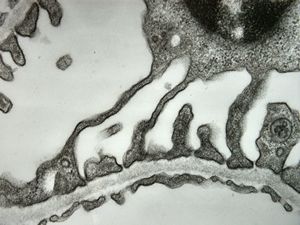

normal kidney - mouse(endothelium and podocytes)

normal kidney - mouse(endothelium and podocyte)